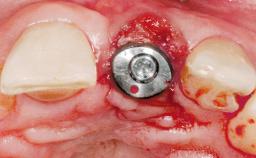

A 30-year-old female patient had lost tooth 21 and was referred to our clinic for consultation and treatment. Due to advanced apical infection, tooth 21 had been extracted two months earlier at another clinic and an acrylic-resin tooth had been bonded to the adjacent teeth. The patient desired implant treatment to avoid any damage to the adjacent natural teeth. While the patient had no history of any systemic disorder, she was a heavy smoker and exhibited medium to advanced periodontitis in the entire jaw. After the initial treatment to achieve a pocket probing depth of less than 4 mm and no bleeding on probing, a decrease in the height of the papillae mesial and distal to the extraction site and overall gingival recession were observed.